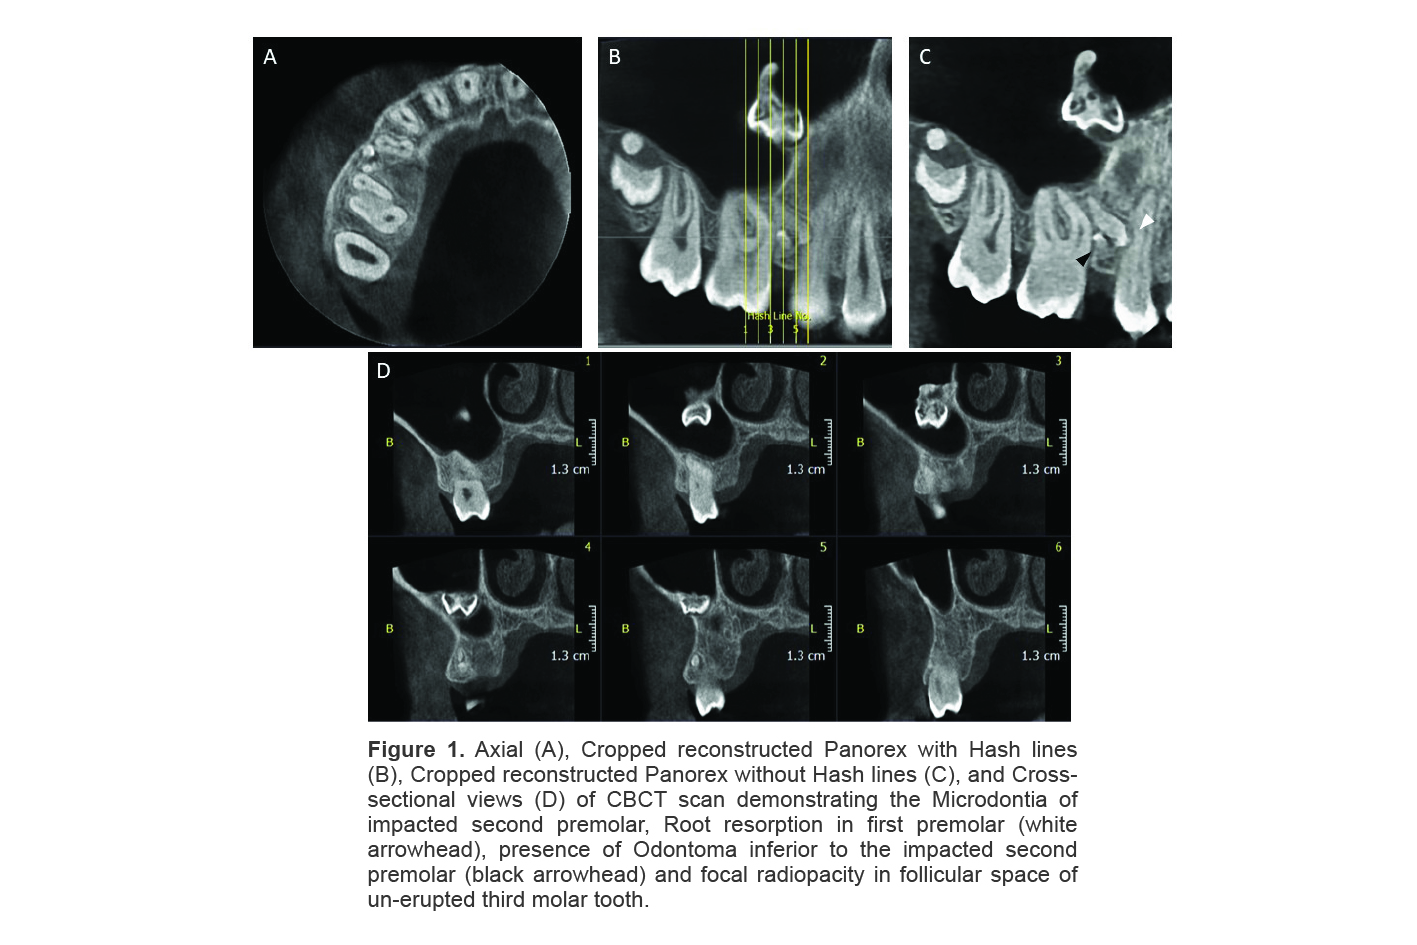

A 13-year-old male patient was referred to our radiology clinic with eruption failure of the permanent maxillary right second premolar tooth (#4 in universal system), while the contralateral second premolar was erupted at the age of 12. Patient had no related symptoms in the right side of face. No signs of redness or swelling of the overlying mucosa was observed in intraoral examination and the medical history of patient was non-contributory. Panoramic radiograph revealed signs of an ectopic tooth in maxillary sinus. CBCT scan was performed with Scanora 3D (Sordex, Finland, FOV 6 x 6 cm, voxel size 150 µm) for further investigation. The second premolar was detected as an impacted tooth in contact with apical third of root of the first premolar. The impacted tooth was reduced in size (microdontia) and had caused root resorption of the first premolar. CBCT reports also represented a small odontoma adjacent to the impacted second premolar. A round radiopaque entity was detected in follicular space of un-erupted right third molar, as an incidental finding (Figure 1). Examination of the maxillary sinus revealed the presence of ectopic primary second molar attached to the anterior and medial walls of the right maxillary sinus, with severe internal resorption (Figure 2). Patient was referred to the oral and maxillofacial surgeon and orthodontist. The ectopic tooth was planned to be extracted under general anesthesia. Although the patient was explained about the consequences of retaining the impacted ectopic tooth in the sinus, his parents refused the treatment plan and therefore, the patient was advised to be on regular clinical and radiographic follow-ups.

Figure 1. Axial (A), Cropped reconstructed Panorex with Hash lines (B), Cropped reconstructed Panorex without Hash lines (C), and Cross-sectional views (D) of CBCT scan demonstrating the Microdontia of impacted second premolar, Root resorption in first premolar (white arrowhead), presence of Odontoma inferior to the impacted second premolar (black arrowhead) and focal radiopacity in follicular space of un-erupted third molar tooth.